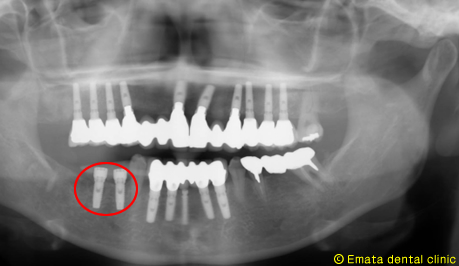

先週行ったインプラント治療は抜歯即時(抜歯してすぐインプラントをいれる)で一回法でおこないました。

向かって左側です。

術前 |